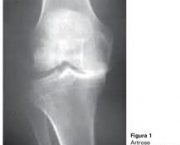

Diagnóstico de Artrose no Joelho

Além de considerar os sintomas relatados pelo paciente o médico pode solicitar exames como Raio-X das articulações que estão comprometidas. As radiografias simples são de grande utilidade nesses casos.